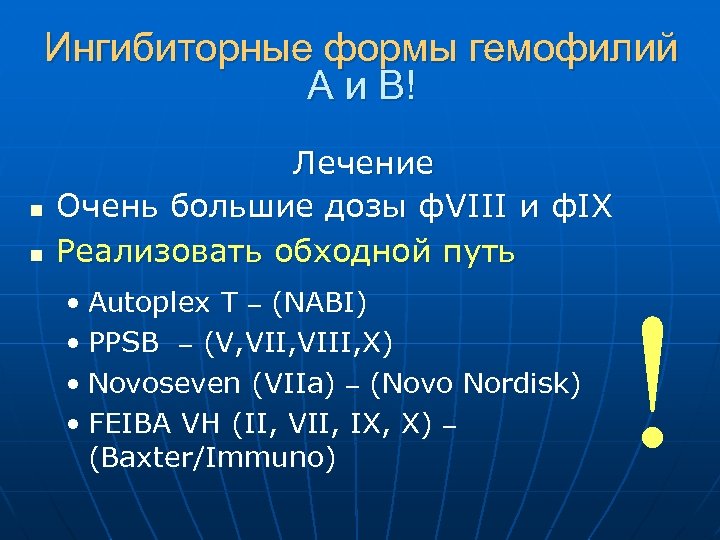

Ингибиторные формы гемофилий А и В! n n Лечение Очень большие дозы ф. VIII и ф. IX Реализовать обходной путь • Autoplex T – (NABI) • PPSB – (V, VIII, X) • Novoseven (VIIa) – (Novo Nordisk) • FEIBA VH (II, VII, IX, X) – (Baxter/Immuno) !